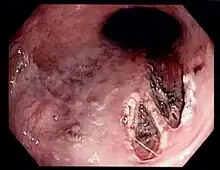

| Mallory–Weiss tear affecting the esophageal side of the gastroesophageal junction | |

Mallory–Weiss syndrome or gastro-esophageal laceration syndrome refers to bleeding from a laceration in the mucosa at the junction of the stomach and esophagus.[1] This is usually caused by severe vomiting because of alcoholism or bulimia,[2] but can be caused by any condition which causes violent vomiting and retching such as food poisoning. The syndrome presents with hematemesis. The laceration is sometimes referred to as a Mallory–Weiss tear.

Definitive diagnosis is by endoscopy of the esophagus and stomach.[9] Proper history taking by the medical doctor to distinguish other conditions that cause haematemesis but definitive diagnosis is by conducting esophagogastroduodenoscopy.[10][11][12]